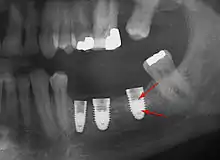

Bone loss (peri-implantitis) on implants over 7 years in a heavy smoker

Fracture of abutment screws (arrow) in 3 implants required removal of the remainder of the screw and replacement.

Cement peri-implantitis

Dental cement under the gingiva causes peri-implantitis and implant failure.